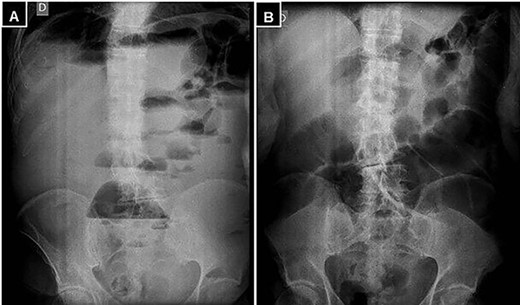

A supine and upright plain X-ray of the abdomen were obtained and showed dilated small bowel loops, mainly in the left upper abdomen, along with multiple air-fluid levels (Fig. 1). Computed tomography (CT) demonstrated significant air-fluid distention of the entire small bowel, up to the right flank and periumbilical region, where a change in caliber was observed (Fig. 2). The findings corresponded to small bowel obstruction (Fig. 3).

Abdominal and pelvic CT with intravenous contrast. (A) Axial image illustrating a change in caliber (black arrow) with subsequent distension of the small intestine, and (B) a small mesenteric collection (black arrow).